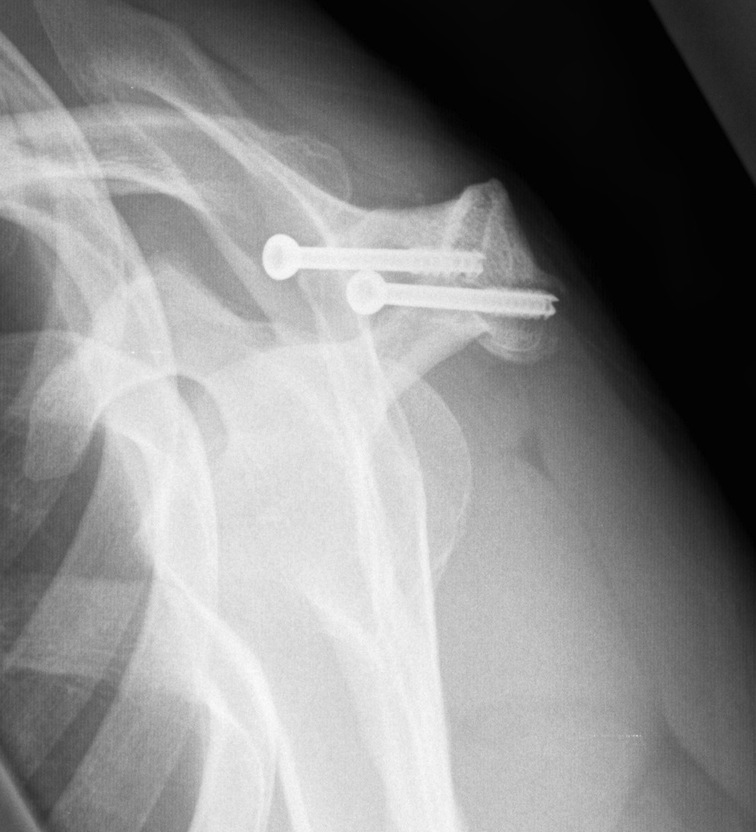

X-ray

Best seen on axillary lateral

Axillary lateral showing meso-acromion Scapula lateral xray showing os acromiale